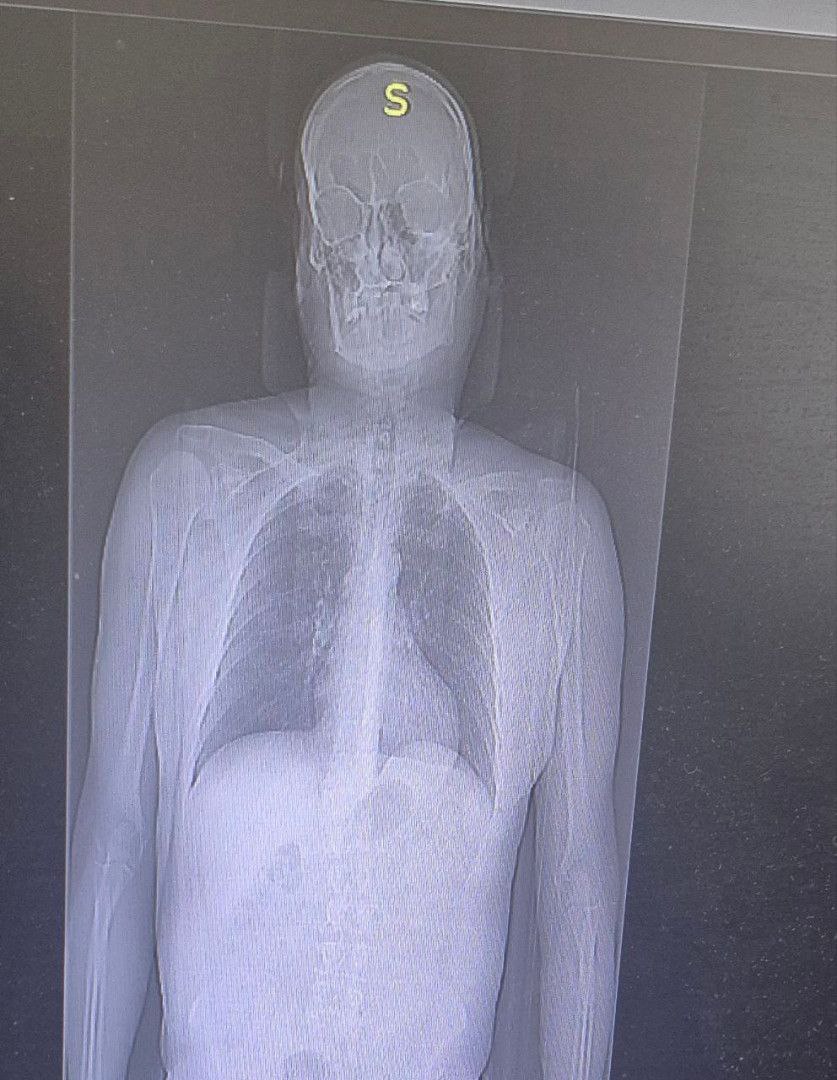

Диагноз: перелом двух рёбер и ушибы. Врачи просят всех любителей острых ощущений не рисковать здоровьем и жизнью ради эффектных фотографий.